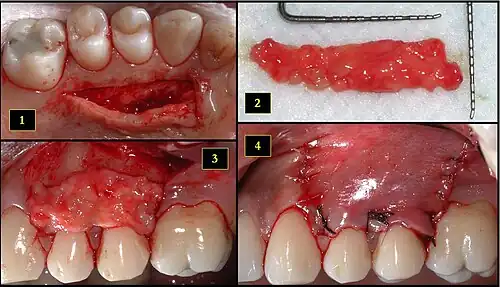

Subepithelial connective tissue graft

- Recipient site exhibits gingival recession on both premolars and first molar (molar recession is not an esthetic issue and will not be treated)

- Incisions prior to flap reflection

- Full thickness flap elevated

- Another viewpoint of the flapped recipient site

- Ipsilateral palatal mucosa serving as the donor site

- The retrieved connective tissue, approximately 25 × 6 mm in dimension

- Connective tissue placed at recipient site

- Recipient site flap coronally advanced and sutured to entirely cover the graft